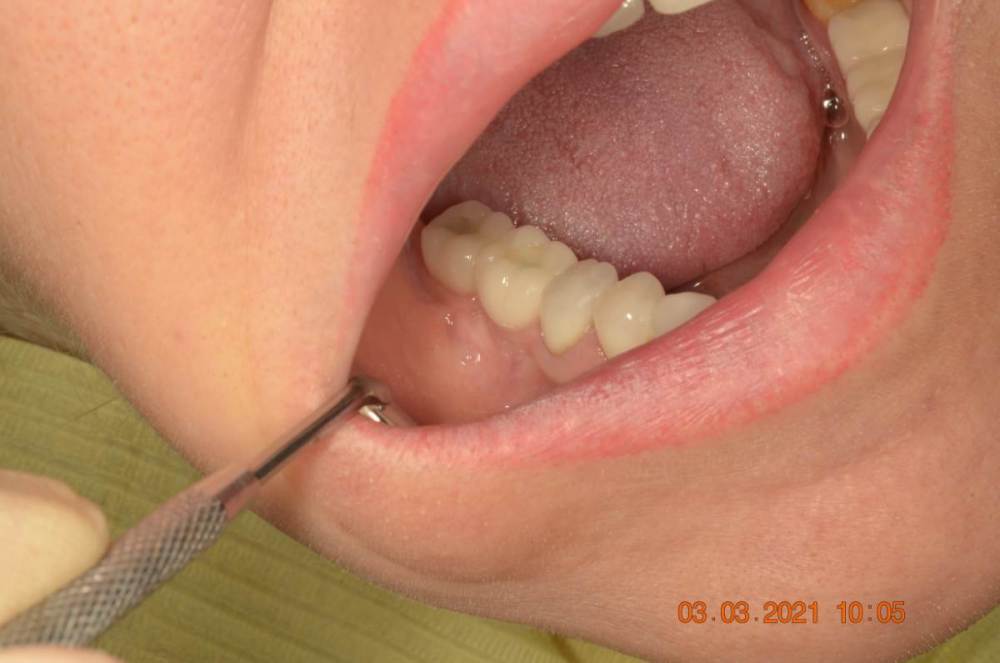

Большой Зеленый Опубликовано 15 августа, 2023 Поделиться Опубликовано 15 августа, 2023 Винтовая фиксация . 8 лет наблюдений .Полет нормальный. Немного прокрасились пломбы в шахтах. Пациентка довольна и счастлива. Привела уже вагон беззубых друзей и родственников. P/S. Система имплантов Ирис...:) 1 Ссылка на комментарий